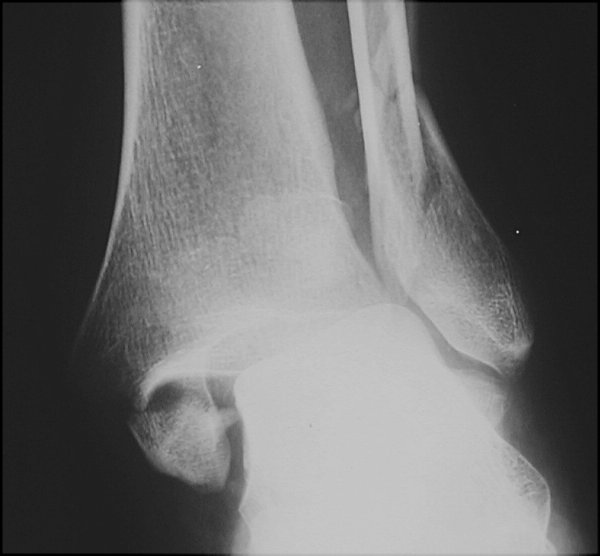

Return to Trimalleolar Fracture